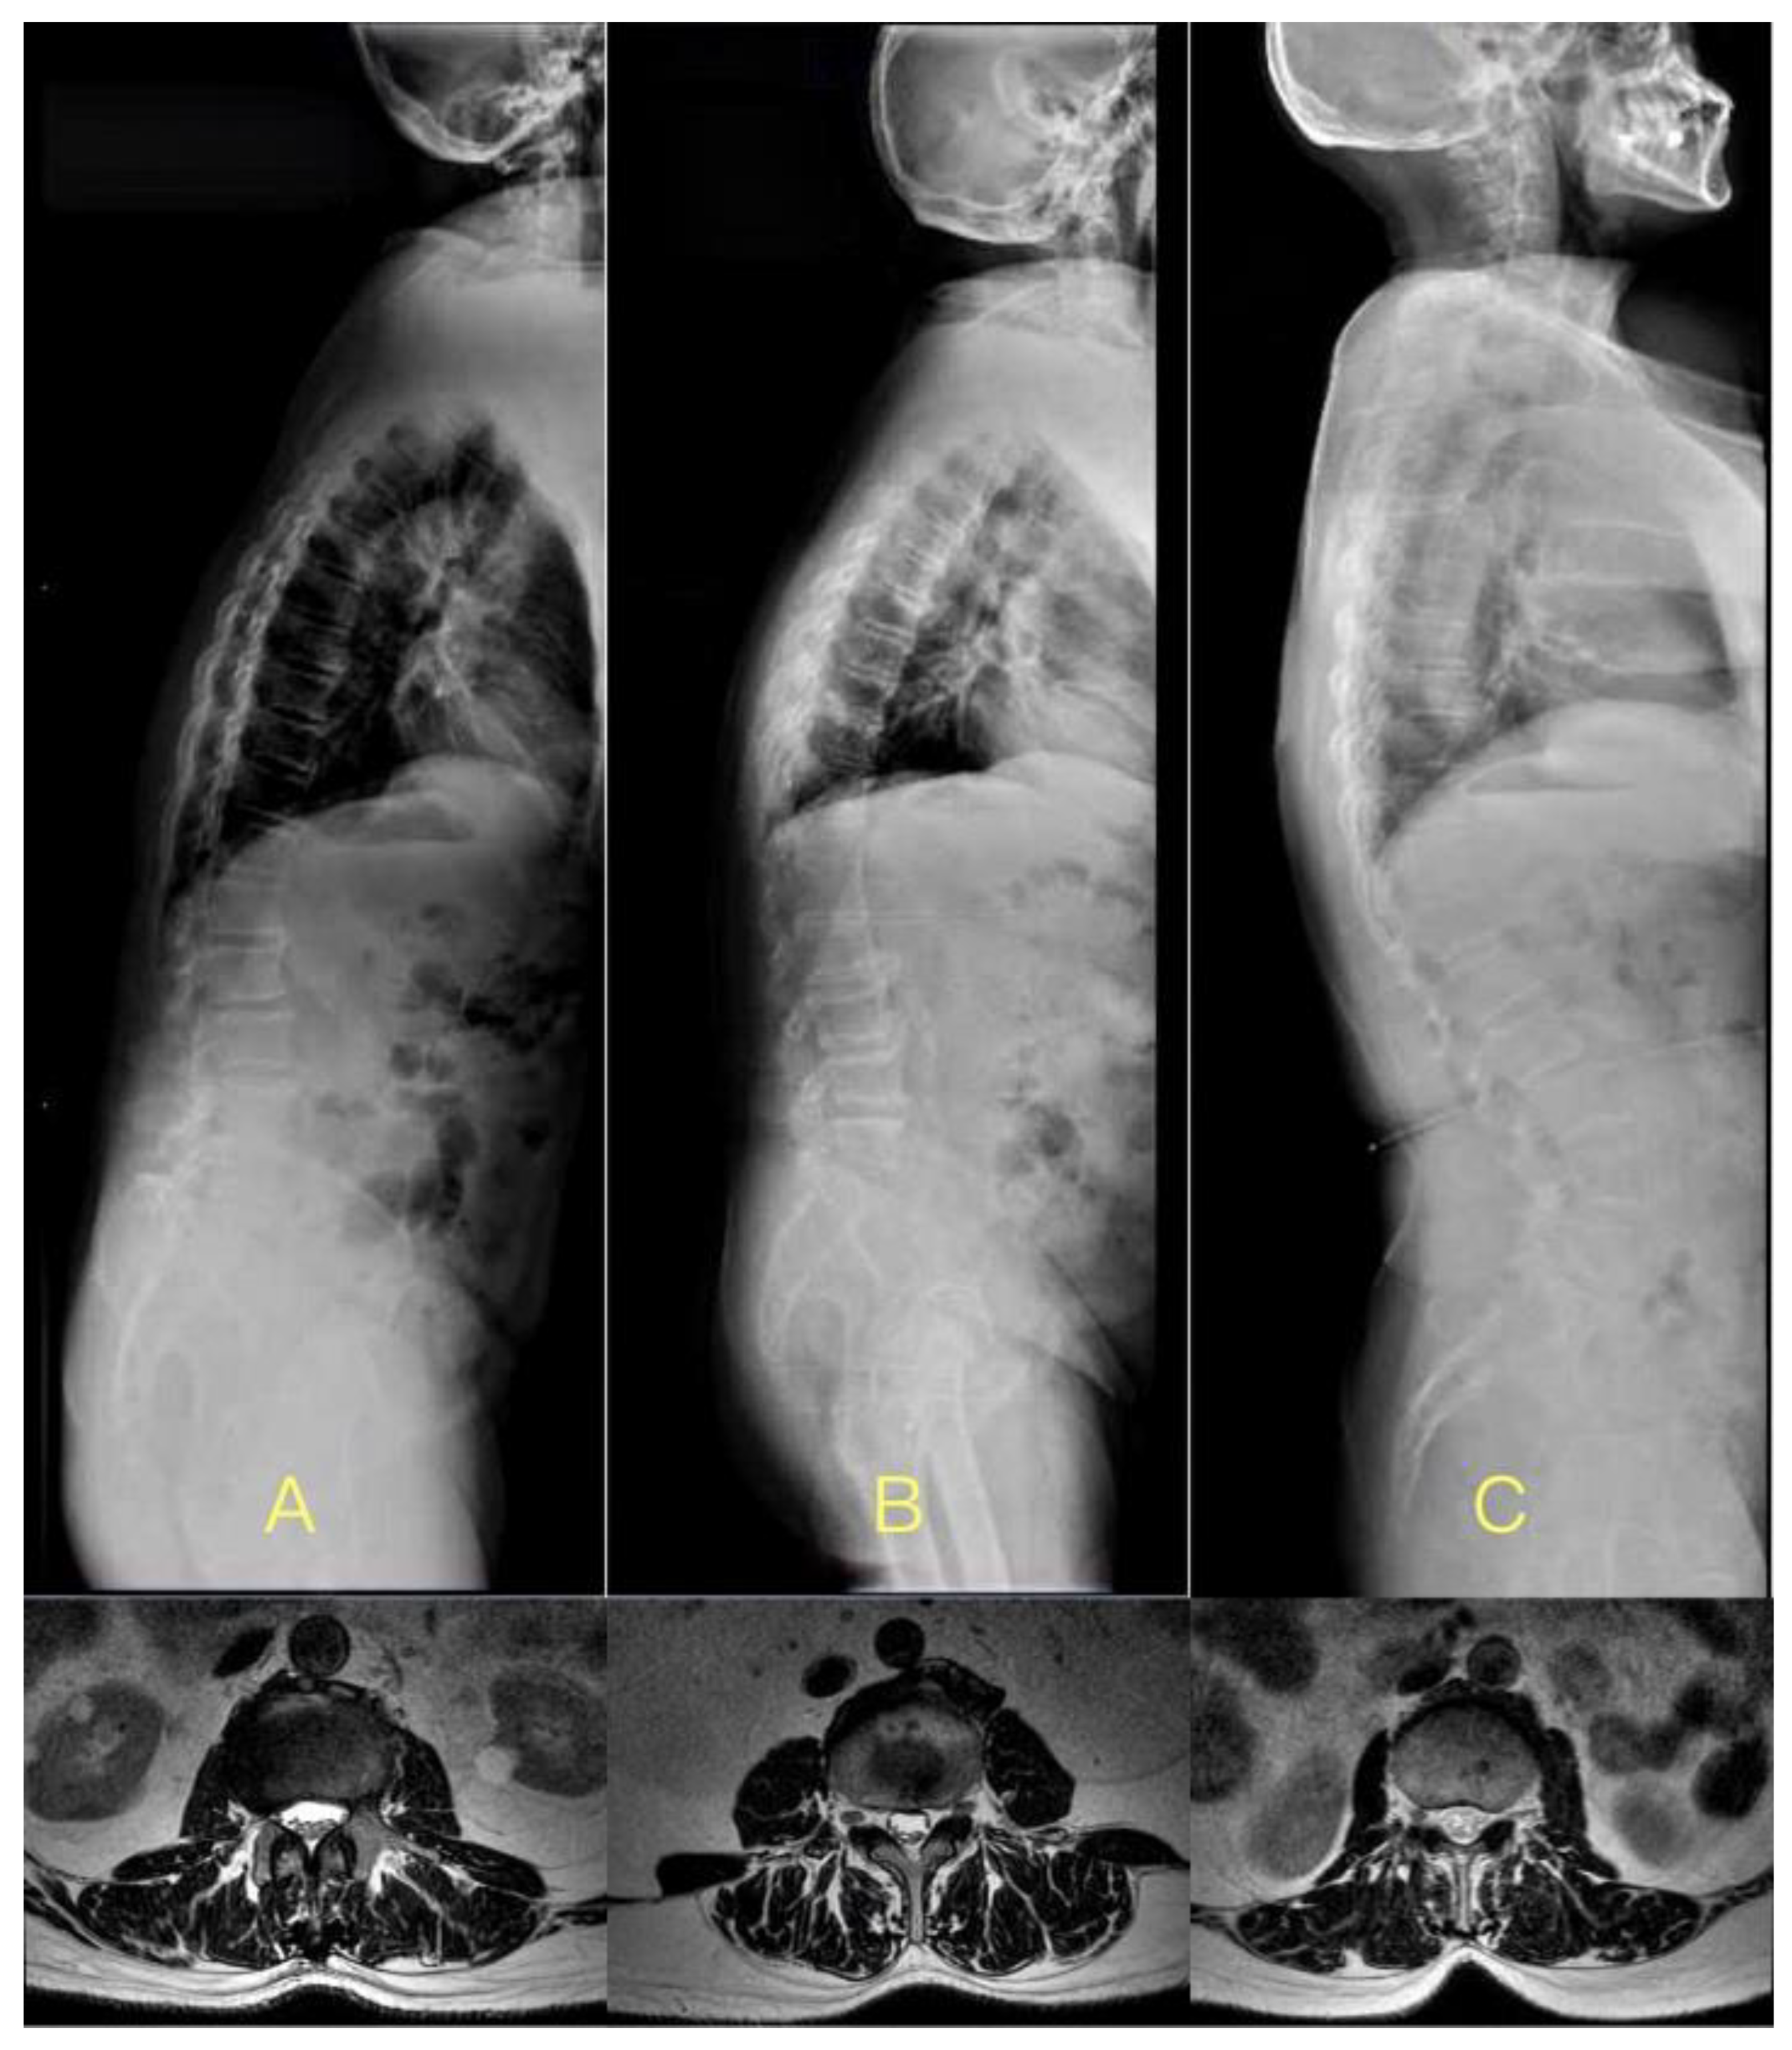

:1. Introduction

2. Materials and Methods

2.1. Participants

2.3. MRI

2.4. Parameters Measurement